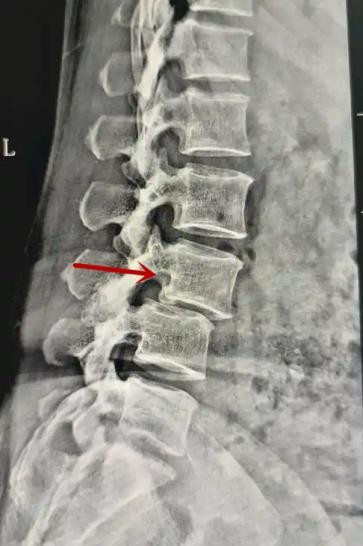

利器一:X線/DR

腰椎X線片作為最基礎(chǔ)的影像檢查手段,利于X線穿透人體組織后成像,以其快捷、直觀、價(jià)格低廉的特點(diǎn),X線檢查主要包括腰椎正側(cè)位、雙斜位以及過(guò)伸過(guò)屈位。主要用于觀察腰椎骨骼的情況,如椎體是否有骨折、骨質(zhì)增生程度、生理曲度的變化、椎體移位的情況等。然而,X線檢查也有它的局限性,無(wú)法判斷是骨折的新舊,對(duì)于椎體內(nèi)部結(jié)構(gòu)和周圍肌肉韌帶組織(如脊髓神經(jīng)、椎間盤、韌帶等)的顯示不佳,另外X線作為有輻射檢查,孕婦及嬰幼兒謹(jǐn)慎選擇。

箭頭提示腰1椎骨折

箭頭提示腰3椎體滑脫